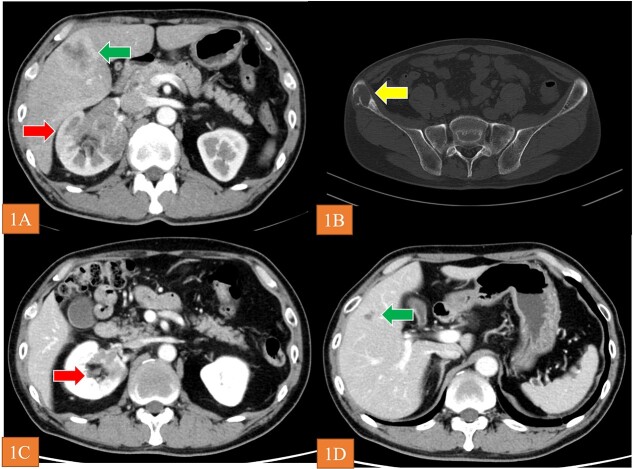

A 56-year-old man visited a previous hospital due to an 8-month history of back pain. Contrast-enhanced computed tomography revealed a hypovascular solid mass in the right kidney and right lobe of the liver as well as osteolysis in the right ilium and lumbar spine at L4 (Fig. 1A and B). He was referred to shimane university hospital (Shimane, Japan) for further evaluation and treatment. His medical history was unremarkable. Blood tests revealed low hemoglobin level (10.7 g/dl), high blood platelet level (55.8 × 104/μl), high C-related protein level (12.86 mg/dl), normal serum calcium level, and normal neutrophil counts. Urine test showed no microhematuria. The Karnofsky performance status was 90%. We then performed needle biopsy of the tumor in the right lobe of the liver. Histopathological findings for the specimen revealed unclassified RCC. There was no metastasis to the brain according to MRI. Accordingly, we diagnosed the patient with RCC at TNM stage cT3aN1M1. Based on the International Metastatic RCC Database Consortium risk classification, his risk was classified as poor. We selected IPI plus NIVO combination as the first-line systemic therapy. Because the patient was diagnosed with grade 1 myocarditis (CTCAE Version 5.0) after two courses of treatment, we halted administration of IPI plus NIVO. Instead, we started CABO 40 mg/day as second-line systematic therapy. The tumor volume decreased by 46% at 40 weeks (Fig. 1C and D), and the best overall response of CABO was a partial response within 73 weeks (RECIST Version 1.1). When disease progression was observed during CABO treatment, we prescribed axitinib 10 mg/day as third-line therapy. Utilizing FoundationOne Liquid on peripheral blood samples, we conducted an analysis of genetic mutations to aid in determining a more efficacious treatment approach. This analysis revealed a germline FH mutation (NM_000143.4) c.1189G>A (p.Gly397Arg) and we diagnosed as HLRCC-associated RCC. After AXI was no longer effective, we administered NIVO alone as fourth-line therapy. The patient is still alive as of March, 2023 (27 months after the start of treatment).

Figure 1.

(A and B) CT revealed the renal tumor (arrow), liver tumor (arrow), and bone metastasis (arrow). (C and D) arrows show that the tumor volume decreased by 46% at 40 weeks after initiation of CABO.